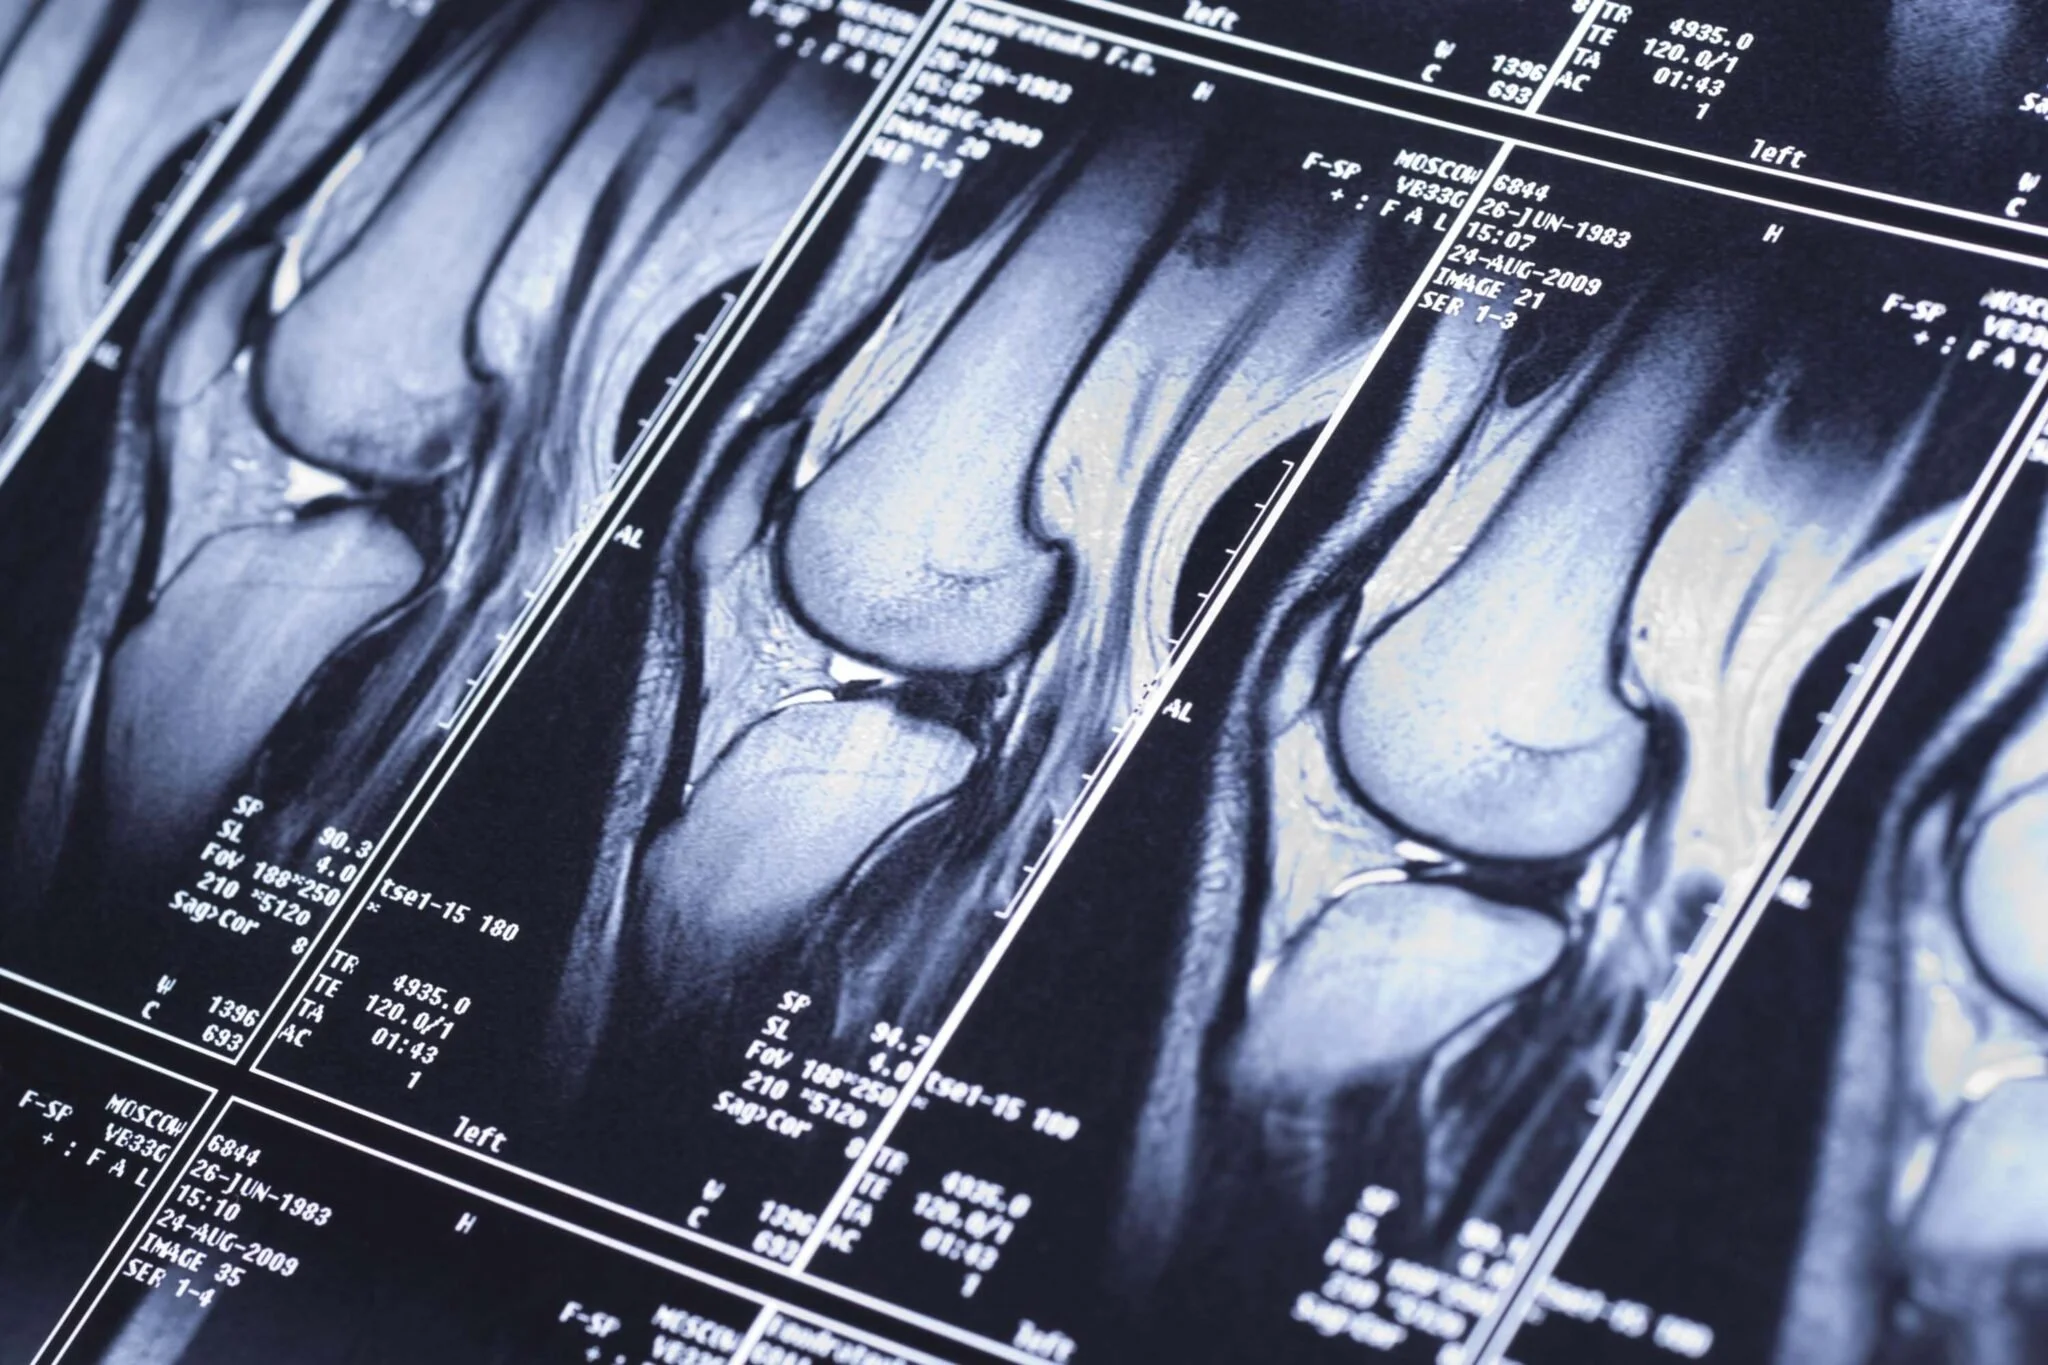

Medical MRI scans of a human knee joint